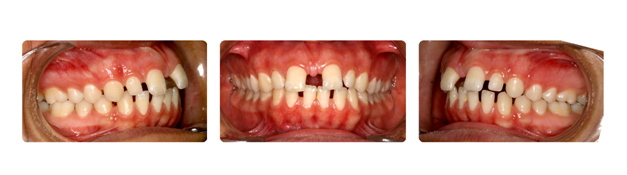

| فک پایین بیمار جلوتر از فک بالا قراردارد وهمچنین دندانهای فک بالا پشت دندانهای پایین قرار گرفته است ودندانهای نیش فک بالا بصورت نهفته می باشد: |

![]() |

| دندان نهفته ی نیش سمت راست در قسمت کام وسمت چپ در زیر لب و بالای دندانها قرار دارد که توسط جراح لثه روی آن برداشته شده وتوسط ارتودنسی و براکتها به جای برده می شود: |